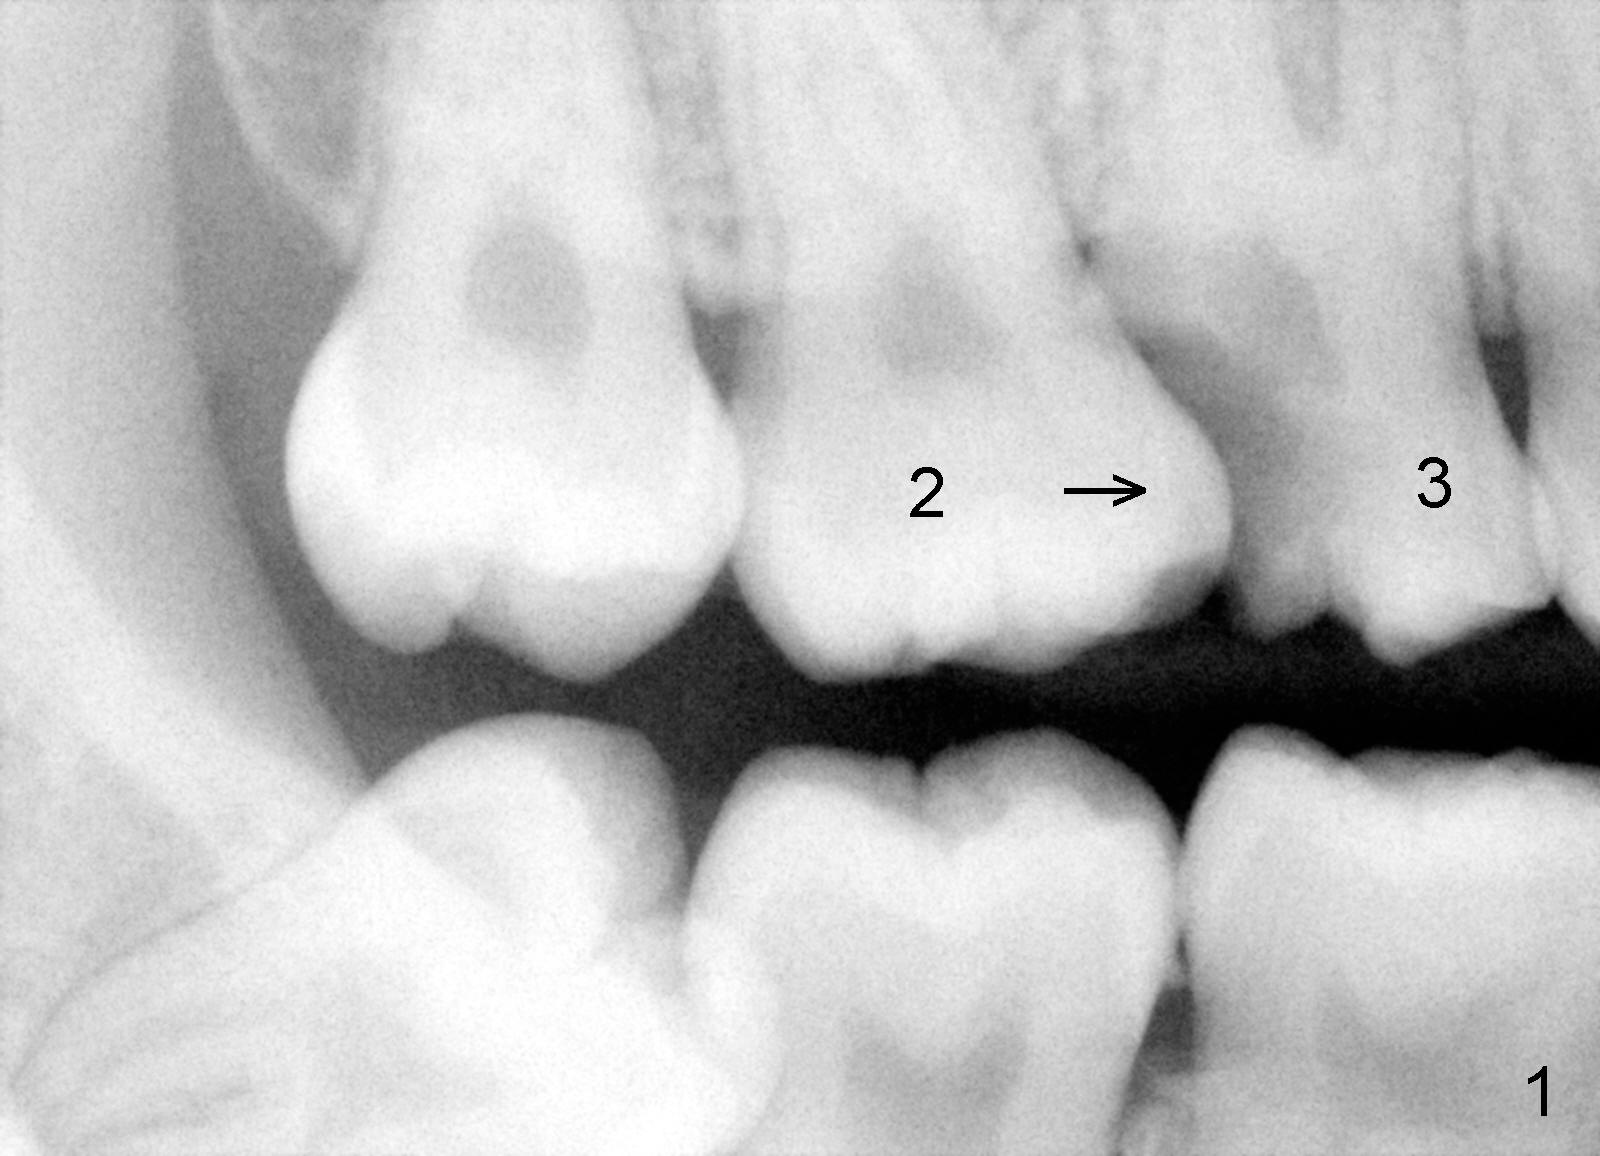

A 19-year-old female requests implant replacement for the tooth #3 (Fig.1). Due to large defect of the carious lesion on #3, the tooth #2 has shifted mesially (arrow).

Fig.3 shows the implant 3 months post placement. It is not placed too superficial. The tooth #2 appears to be more distalized (using a lingual button as mesial fixed point (Fig.3 <)) than that in Fig.2.